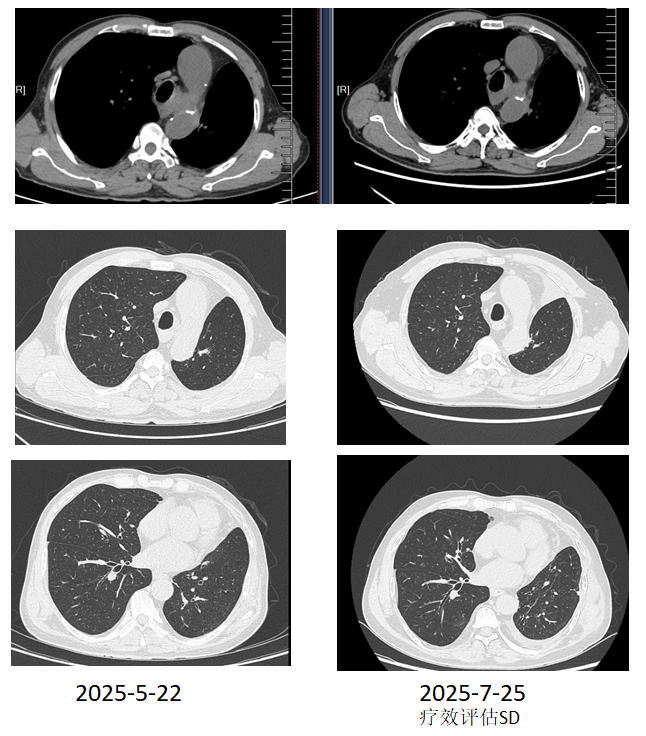

2025年5月,复查胸部CT提示,纵膈淋巴结大者短径16mm,左肺门淋巴结压迫左肺下叶支气管。

2025-5-6,开始化疗联合免疫治疗3周期,具体用药方案:长春瑞滨软胶囊+奈达铂+替雷利珠单抗。

2025-7-17,予长春瑞滨软胶囊+替雷利珠单抗治疗维持至今(末次治疗时间2025-8-18)。

疗效评估:SD。